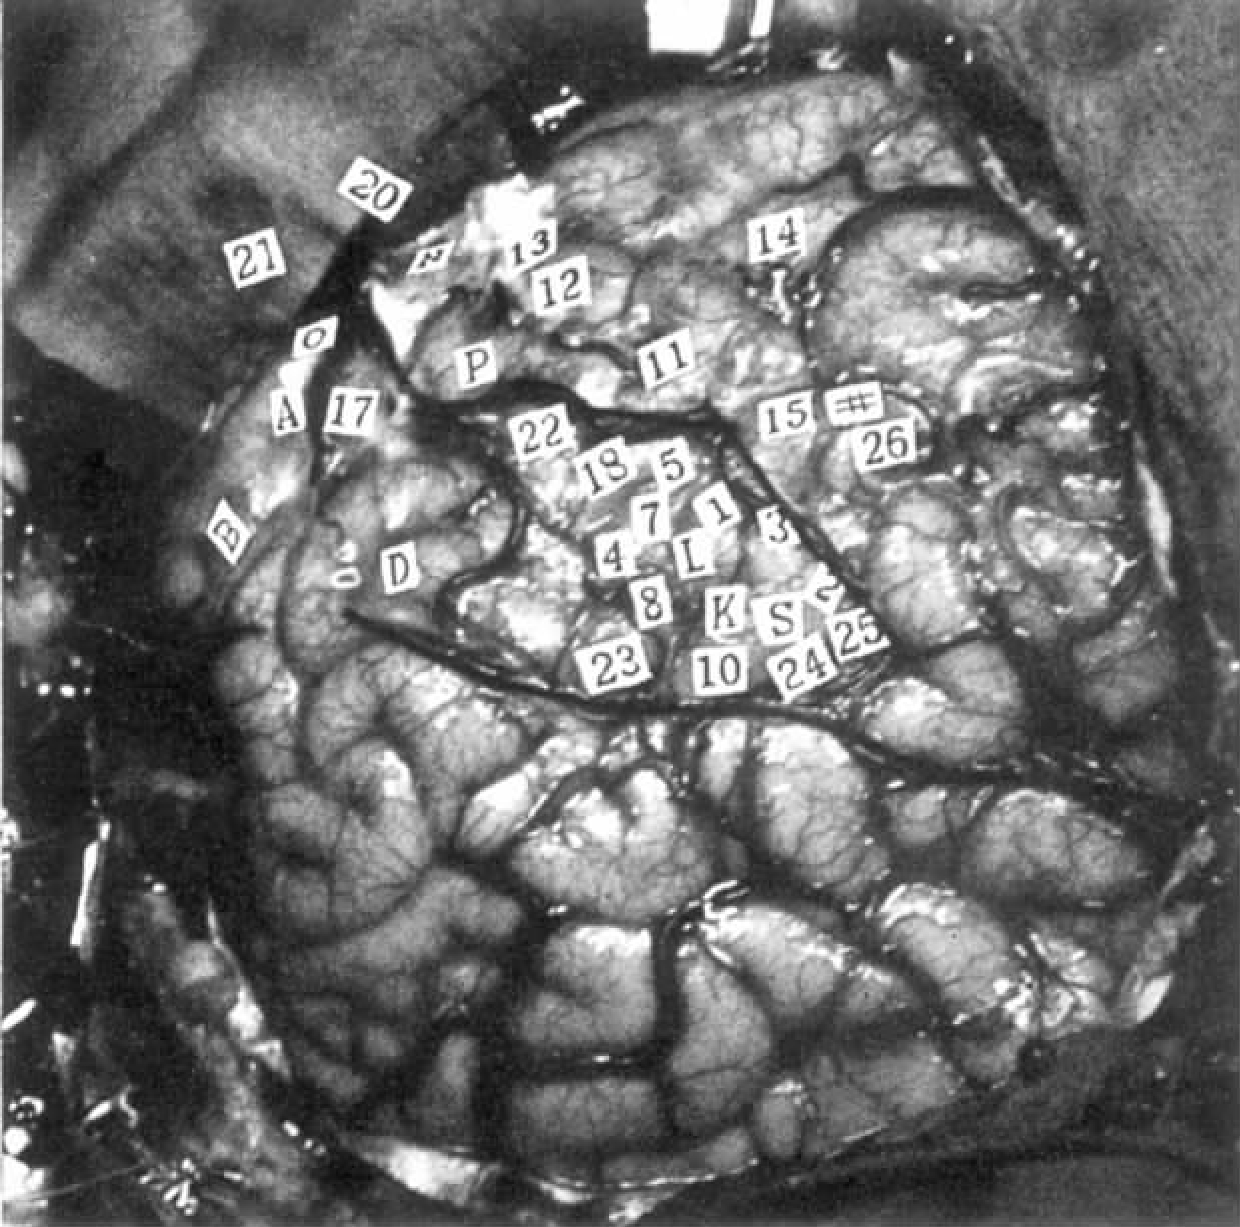

病例2 H.E.

这是位23岁的男性患者,他患有继发于左额叶外伤引起的局灶性皮质癫痫。癫痫发作的诱因是对侧肢体运动。

左脑,近中央沟处的感觉区,次级感觉区(见图4-2)。

图4-2 病例H.E.双侧都有次级感觉反应,也有运动效应

刺激条件:刺激频率60Hz,刺激电压:点1至14为1V,后面的点为2V。

14 左脚趾尖的麻刺感,脑电图显示刺激后皮层电位下降。重复刺激点14,只产生嘴里的感觉。

22 右脚有麻刺感,“就像它睡着了一样。”

22 在患者移动右脚时重复刺激。他产生同样感觉,但刺激并未使移动停止。

23 右腿有麻刺感。

23 重复刺激,对腿的移动无干扰。

24 右手的中间三个手指有感觉,并向手掌扩散。“感觉上它好像睡着了。”在点24上方几毫米处又进行了3次刺激,但没有反应。

24 重复刺激,患者报告他的右手有抽动感。观察到中间的三个手指有轻微伸展。

24 在患者用右手进行挤压动作时重复刺激,可见挤压的力量有些许下降而且手指再次出现运动。

编者注2

本例主要是对患者左脑近中央沟处的感觉区和次级感觉区进行刺激。对次级感觉区的刺激产生对侧和同侧肢体的麻刺感,不伴有随意运动抑制。

刺激点24造成三个手指的感觉,其定位相当精细,因为刺激挪动几毫米,就不显效果,而点24的反应是可以重复的。